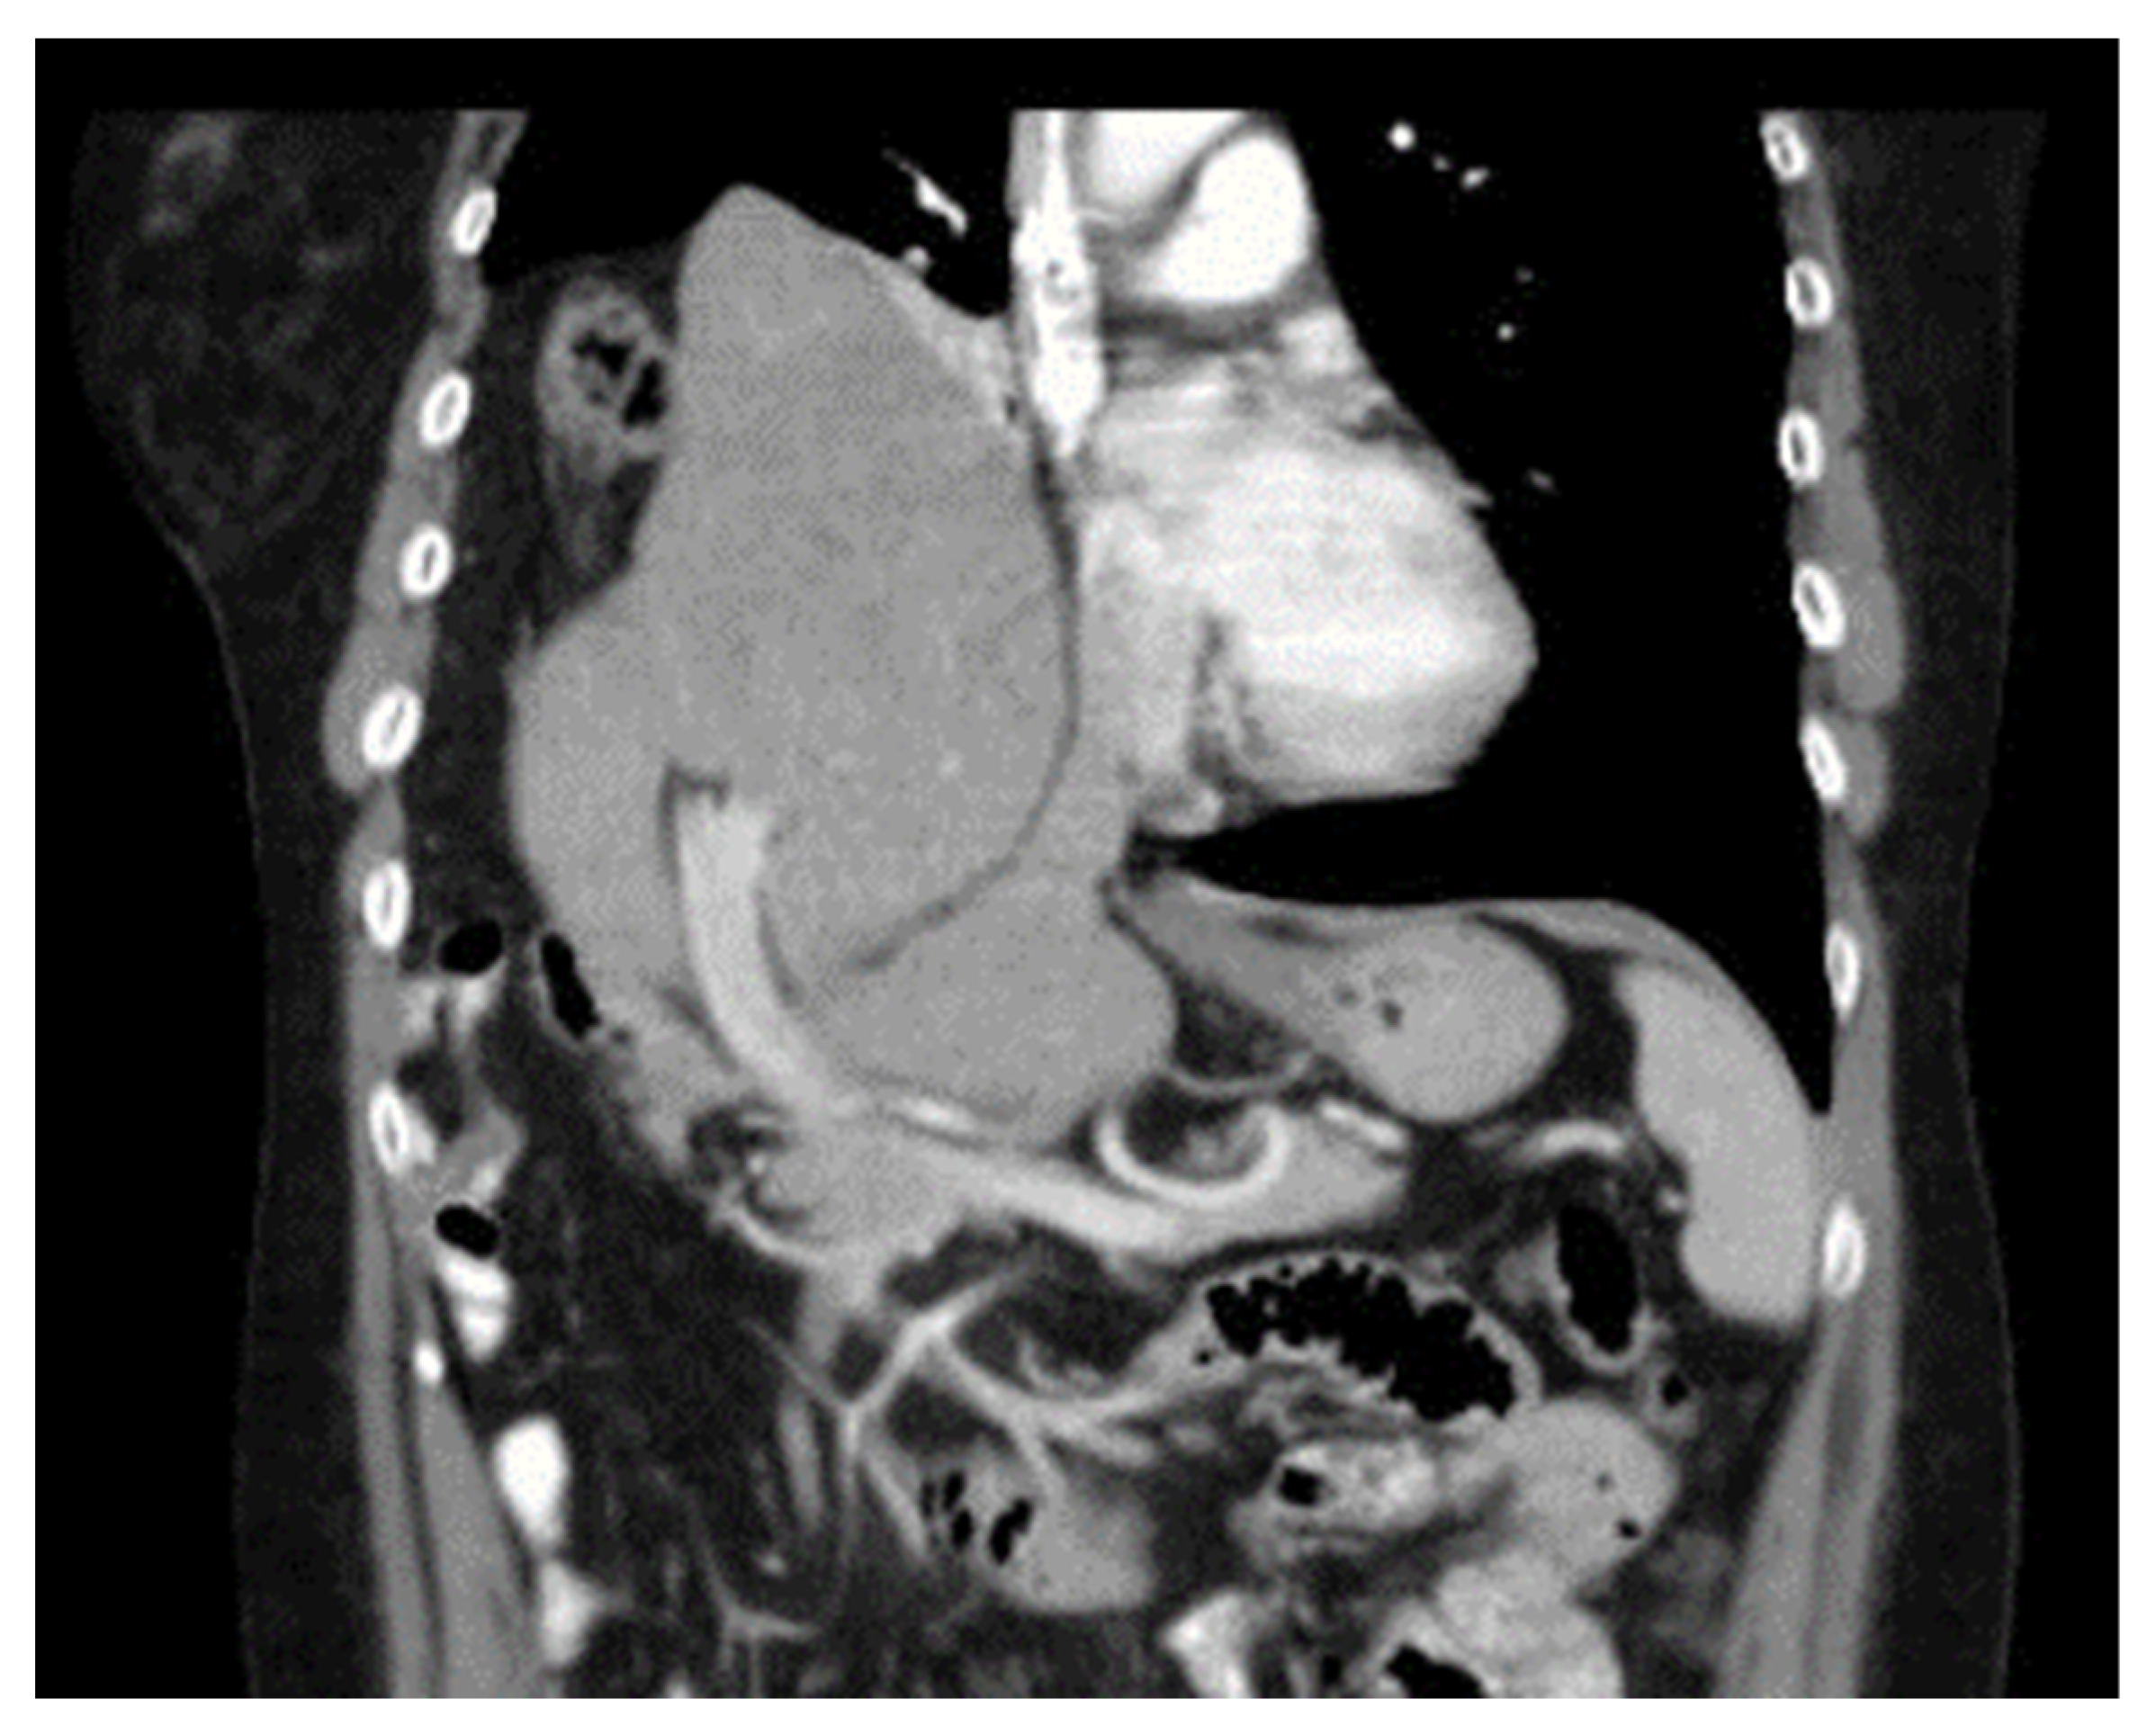

Diaphragmatic Liver Herniation after Radiofrequency Ablation of a Secondary Liver Tumor